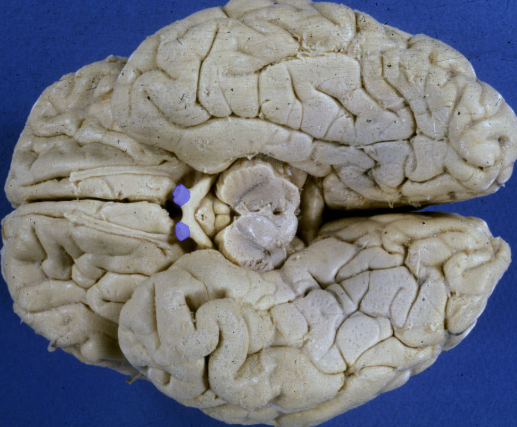

optic chiasm

(note proximity to infundibulum and hypothalamus)

X - loss of vision in the temporal half of both visual fields:

bitemporal hemianopsia3

optic tract

thalamus and the crus cerebri

A lesion of the right optic tract causes a complete loss of vision in the left hemifield:

contralateral “homonymous” hemianopsia.